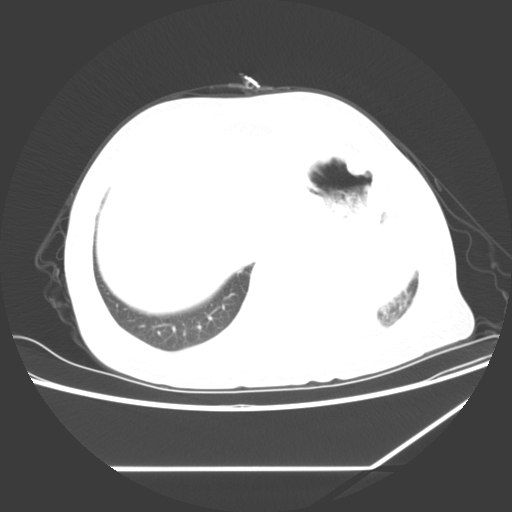

标题: CT25393:病人45岁,咳嗽,吐黄痰带血丝,发热,胸闷月余 [打印本页]

标题: CT25393:病人45岁,咳嗽,吐黄痰带血丝,发热,胸闷月余

1、左肺中央型肺癌并双肺弥漫性转移   2、双肺部感染    3、肺大泡     4、左侧胸腔积液

双侧肺弥漫性病变,可见“空泡征”及“蜂窝征”,考虑肺泡癌可能性大,左侧胸腔积液,考虑胸膜受累可能!

1)不排除肺泡癌可能。2)左侧胸腔积液。